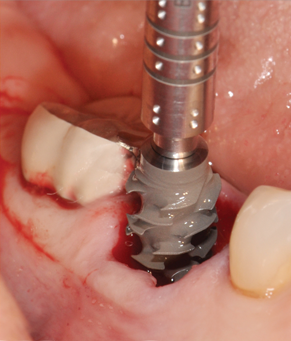

(7.) Restoratively centered guided osteotomy and implant insertion.

Figure 7

(8.) Restoratively centered guided osteotomy and implant insertion.

Figure 8